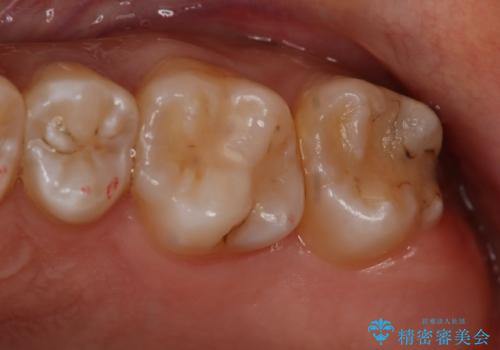

- 左上7番の虫歯治療を主訴に来院された患者様です。

虫歯の範囲が広かったので切削量・形態を考慮し、セラミッククラウンでの治療を計画しました。